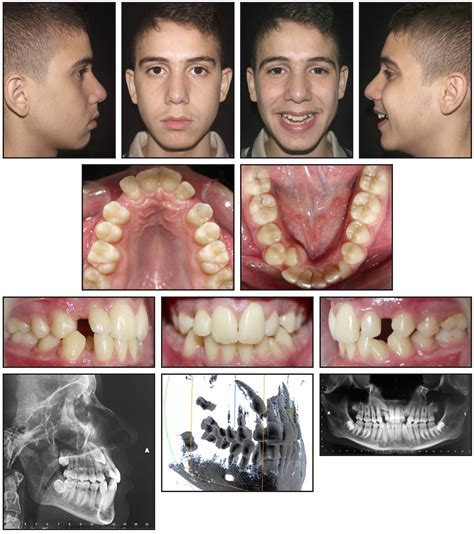

Dental anatomy diagram

The teeth commonly referred to as “K9s” are technically known as canine teeth or cuspids. Located between your incisors (the front teeth used for biting) and your premolars (the teeth used for crushing), these four teeth—two on the top and two on the bottom—serve as the “cornerstones” of your dental arch. They are the longest teeth in the human mouth and are characterized by a single, sharp, pointed cusp designed for grasping and tearing.

In humans, these teeth are not as long or sharp as those found in carnivores, reflecting our evolutionary shift toward a diverse, plant-and-meat-based diet. Despite this, they remain some of the most critical structural components of your bite. They help guide the jaw into the correct position when you close your mouth and provide necessary support for the surrounding facial muscles.